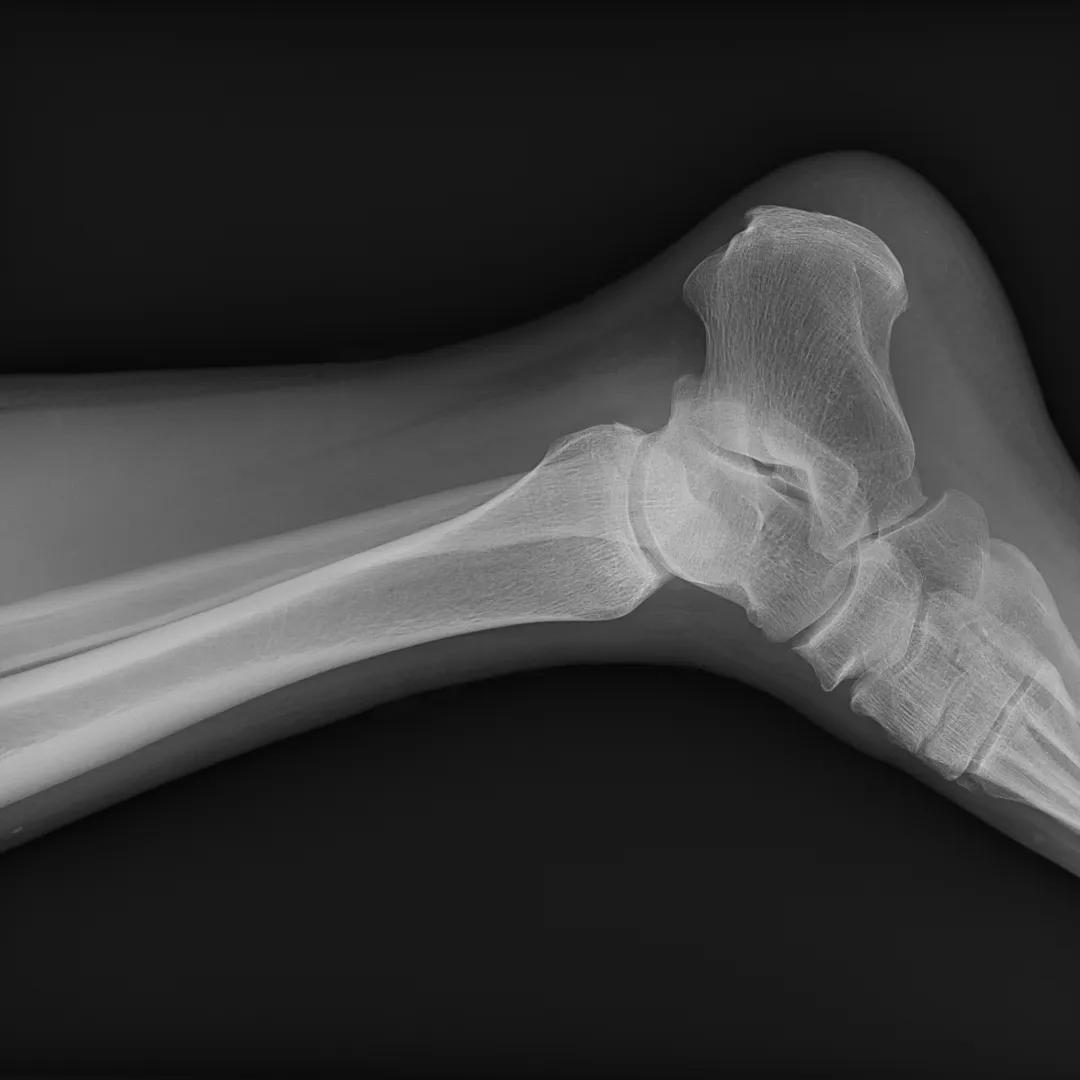

配备4.0lp/mm超大空间分辨率无线平板,清晰呈现拍摄部位组织细节,实现临床精准诊断。

最后来看看“飞燕”的临床成像:

滑动查看更多图片